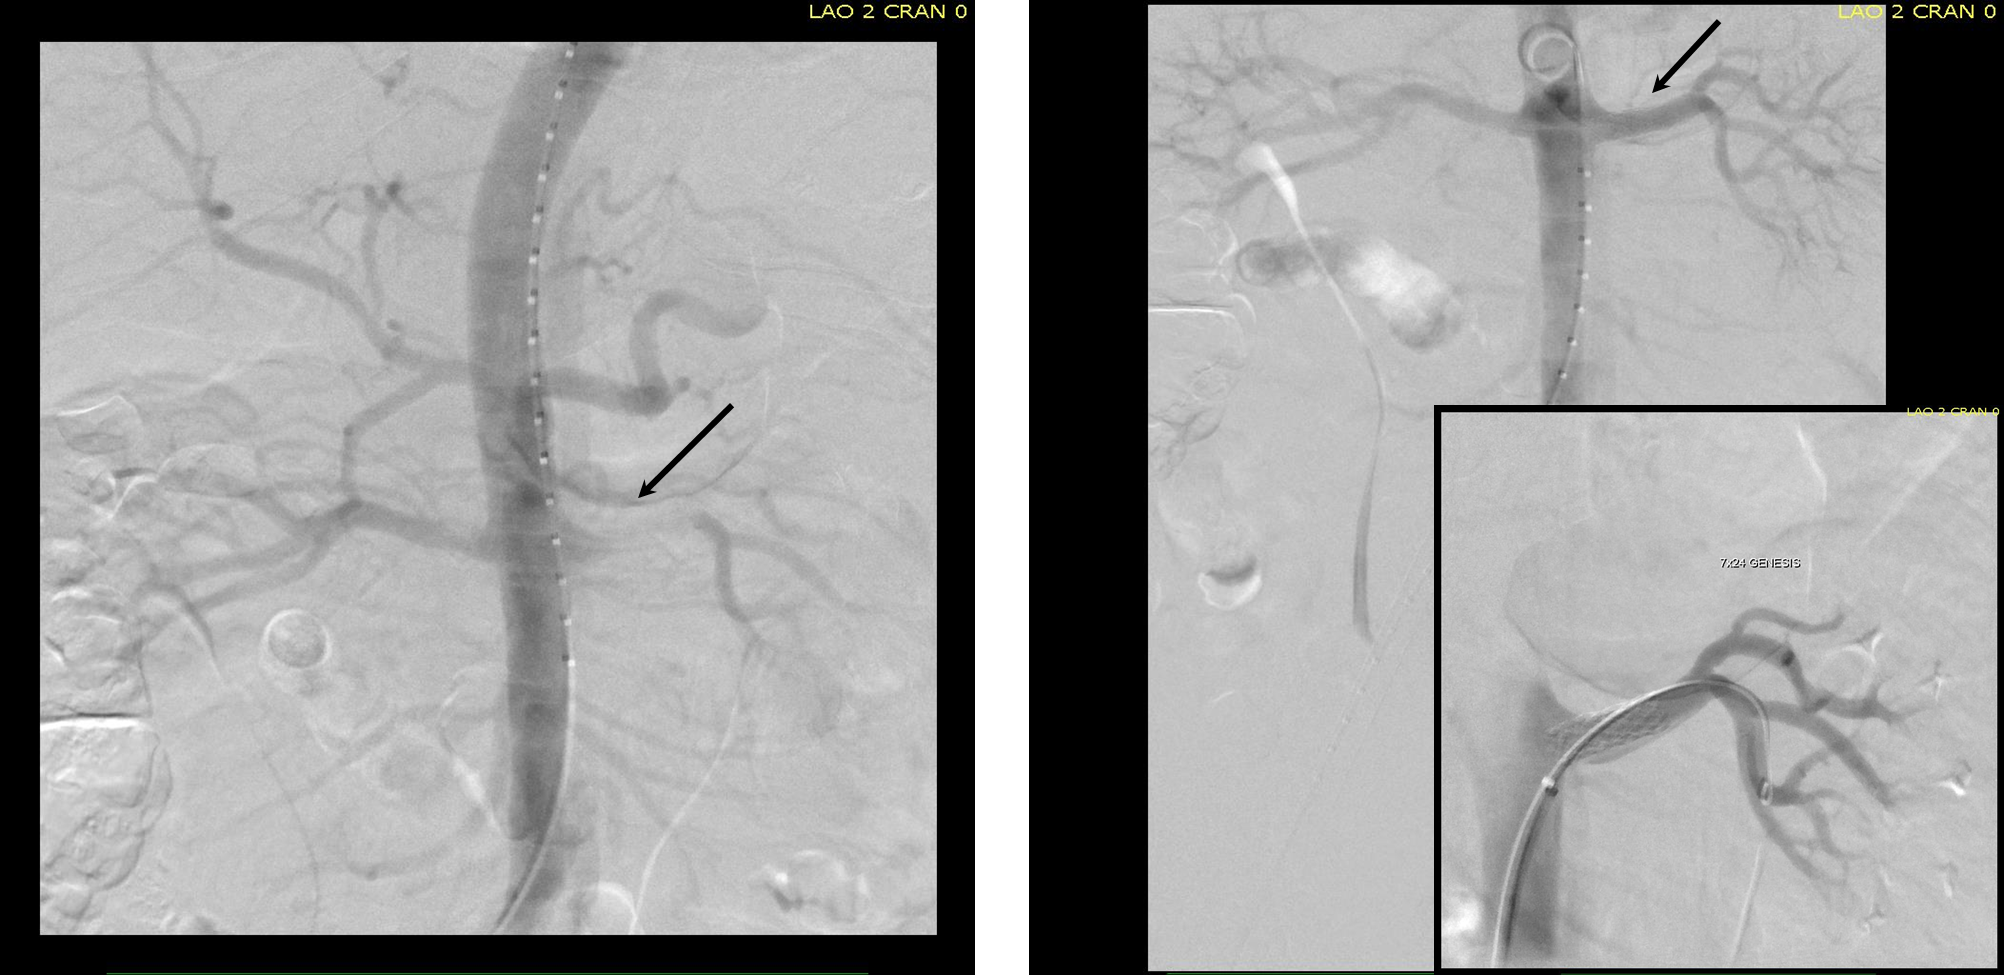

Arteriography from femoral access showed an occlusion of the SMA beyond the middle colic artery, a typical pattern for an embolism that occurs when embolism lodges distally and propogates proximally (image below).

I got Glidewire access into the ileocolic terminus of the SMA, exchanged for a Rosen wire, over which I placed an 8F sheath into the proximal SMA. This was a rather large sheath meant to catch thrombus as I suctioned it out with a 6F Penumbra catheter. This is another technique I borrowed from the neurointerventionalists. Whenever a stroke alert is going on, curiosity drives me to peak in and see what marvelous gadget or gewgaw they are using, and I was impressed by how efficiently the neurointerventionalists were able to get to the smallest thrombus in the furthest branch vessels. I was prepped for open thrombectomy, consented for bypass if necessary, but having experience in suctioning clot through single catheters and sheaths, I thought the simple design of the Penumbra and its efficacy in the cerebral system could easily translate into the mesenteric.The problem with open thrombectomy is the inability to see if you have cleared thrombus from all the branches unless you do an arteriogram after you’ve completed your procedure. This may be a significant contributor to the 20-30% bowel resection rate that occurs on second look laparotomy in my old paper and in the literature since its publication.

The Penumbra was effective in removing much of the fresh thrombus, but I was also cognizant of the fact that pulling out the catheter will draw clot into the 8F sheath that did not make it into the catheter. I placed a wire, and removed the sheath to expel much of the bulky thrombus (picture below).

The completion angiogram (below) doesn’t show the intermediate angiograms showing thrombus that embolized to other arteries as I manipulated the catheters and thrombectomized -I was able to successfully retrieve these with selective catheterization, another neurointerventional series of maneuvers that I have successfully borrowed.